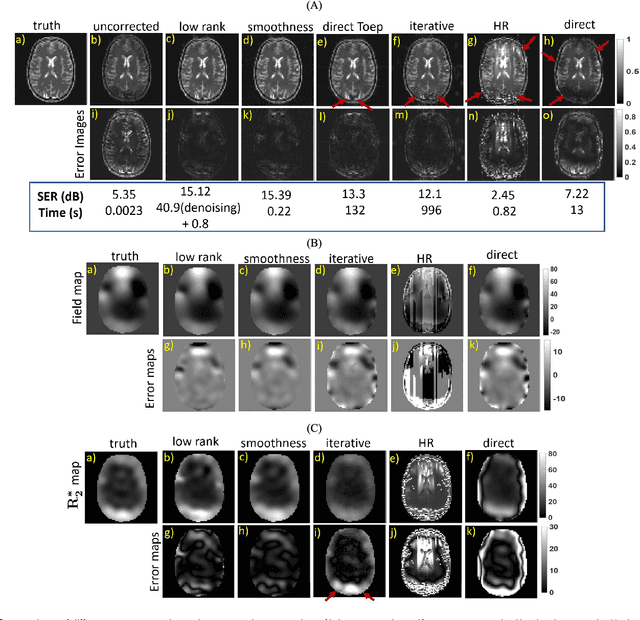

Abstract:We introduce a structured low rank algorithm for the calibration-free compensation of field inhomogeneity artifacts in Echo Planar Imaging (EPI) MRI data. We acquire the data using two EPI readouts that differ in echo-time (TE). Using time segmentation, we reformulate the field inhomogeneity compensation problem as the recovery of an image time series from highly undersampled Fourier measurements. The temporal profile at each pixel is modeled as a single exponential, which is exploited to fill in the missing entries. We show that the exponential behavior at each pixel, along with the spatial smoothness of the exponential parameters, can be exploited to derive a 3D annihilation relation in the Fourier domain. This relation translates to a low rank property on a structured multi-fold Toeplitz matrix, whose entries correspond to the measured k-space samples. We introduce a fast two-step algorithm for the completion of the Toeplitz matrix from the available samples. In the first step, we estimate the null space vectors of the Toeplitz matrix using only its fully sampled rows. The null space is then used to estimate the signal subspace, which facilitates the efficient recovery of the time series of images. We finally demonstrate the proposed approach on spherical MR phantom data and human data and show that the artifacts are significantly reduced. The proposed approach could potentially be used to compensate for time varying field map variations in dynamic applications such as functional MRI.

Abstract:We propose a structured low rank matrix completion algorithm to recover a time series of images consisting of linear combination of exponential parameters at every pixel, from under-sampled Fourier measurements. The spatial smoothness of these parameters is exploited along with the exponential structure of the time series at every pixel, to derive an annihilation relation in the $k-t$ domain. This annihilation relation translates into a structured low rank matrix formed from the $k-t$ samples. We demonstrate the algorithm in the parameter mapping setting and show significant improvement over state of the art methods.